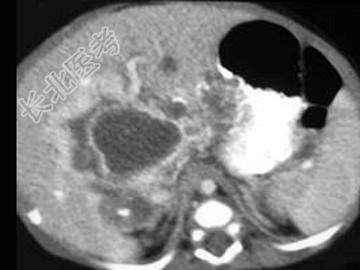

- 单项选择题男,39岁, 进行性消瘦、肝区不适、皮肤巩膜黄染2月,乙肝全套: HbsAg(+),Anti-Hbe(+), Anti-HbcIgG(+),肝功能及AFP均正常, CT检查如图,最可能的诊断是 ( )

A、肝脓肿

B、肝血管内皮瘤

C、肝血管瘤

D、胆管细胞癌

E、肝淋巴管瘤